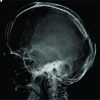

Plain cervical spine radiography (AP and lateral) is falsely suggestive of the absence of an atlas (Fig. 2).